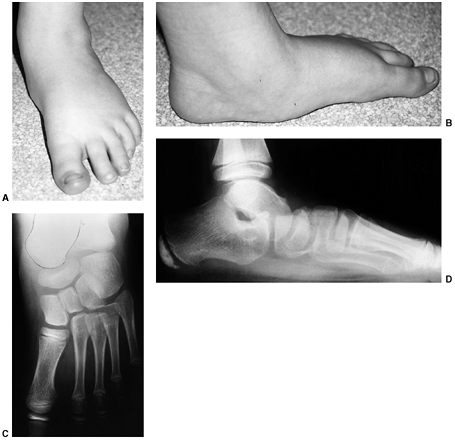

deformity characterized by equinus of the hindfoot and adduction of the

midfoot and forefoot with varus through the subtalar joint complex (Fig. 30.6). There is also a cavus deformity

through the midfoot, which accompanies most clubfeet. In identifying the pathologic tissue in a clubfoot, Irani and Sherman (14) found the talus to be uniformly abnormal, and a group led by Clarke (15)

![]() |

Figure 30.4 A, B:

Hindfoot position is measured as varus or valgus, on the basis of the angle subtended by the longitudinal axis of the tibia and the longitudinal axis of the hindfoot. C: With normal hindfoot mobility as the patient rises on the toes, the calcaneus tips into varus position. |

Figure 30.6 Clubfoot deformity is associated with forefoot supination, deep medial creases, and equinovarus of the hindfoot.

|

Figure 30.7 Clubfoot (left) with single heel crease and healthy foot (right) with multiple heel creases.